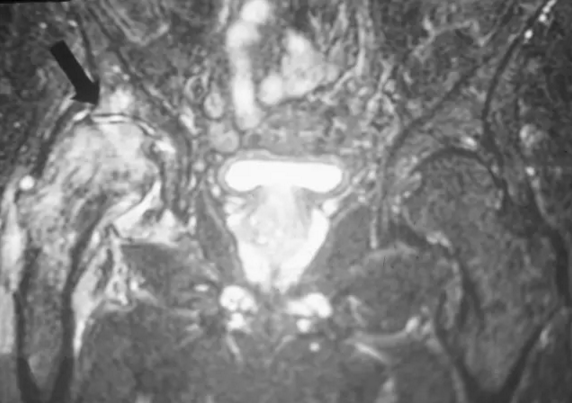

T2压脂像在股骨头和颈部(箭头)内显示增强的信号,代表水肿。 STIR和脂肪饱和成像非常敏感。